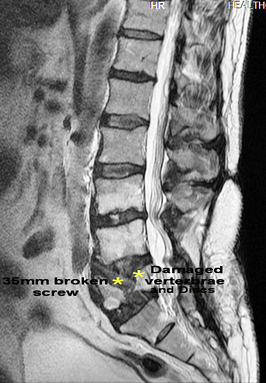

The condecending mental attitude guy was almost saying that a lot of it was in our minds!! After a few sessions I placed my back xray on the dest in front of him and said, this is fact!! All participants cheered!!!